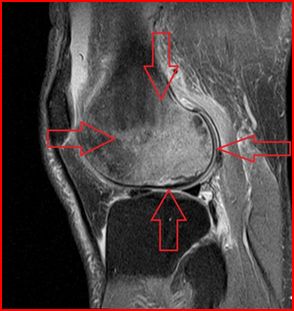

KNEE Posterolateral Corner injuries Of The knee

Posterolateral corner injuries of the knee A SERIOUS INJURY COMMONLY MISSED R. J. Pacheco, C. A. Ayre, specialist knee clinic. MRI correctly identified 14 of 15 injuries when performed acutely cal studies have shown increased force on ... Document Retrieval